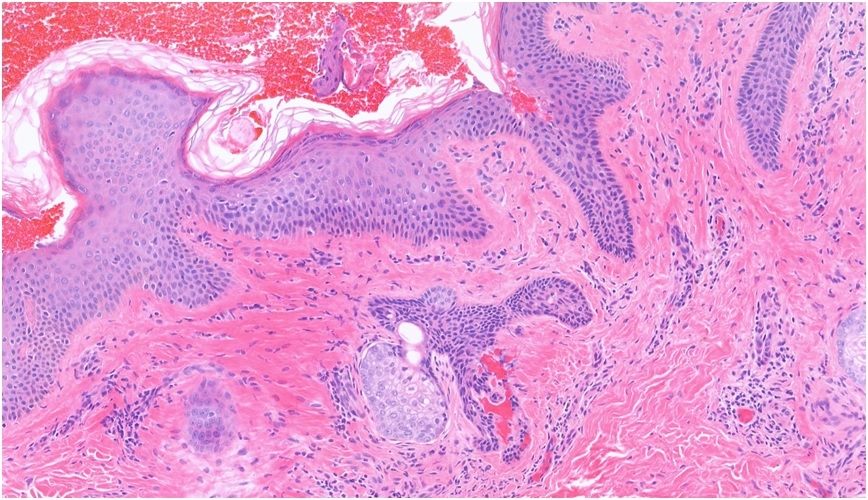

13 M, Left forehead Excision ?Epidermal naevus